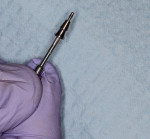

The osteotomy was initiated using a 2.2 mm diameter pilot drill, which is used to penetrate the cortical bone, but not taken to depth (Figure 7). This bur is used to create proper mesial-distal and facial-lingual angulation. To help visualize the eventual emergence profile of the final implant-retained crowns, an MD Guide (Golden Dental Solutions) was employed. These cylinders of five various diameters are used to simulate the mesial-distal width of the natural dentition. The MD Guide enables the drilling of a pilot hole with the desired mesial-distal spacing and parallelism, without altering the current surgical protocol (Figure 8). Should the MD Guide require repositioning, the minimal hole created by the pilot drill will not hamper final site development.